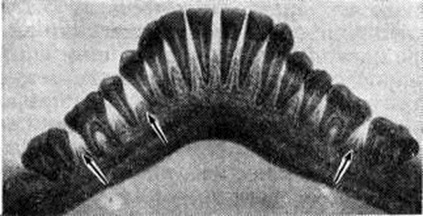

Рентгенологические картина Пародонтоз зависит от стадии процесса. В начальной стадии выявляются остеопороз (смотри полный свод знаний) и деструкция коркового вещества вершин межальвеолярных перегородок. В развившейся стадии отмечается усеченность вершин межальвеолярных перегородок, наряду с горизонтальной появляется и вертикальная резорбция, нередко с образованием костных карманов. Контуры альвеолярных отростков имеют характерный фестончатый, «изъеденный» вид (рис. 4), определяется отложение поддесневого зубного камня. Нарастание патологический процесса проявляется появлением очагов пятнистого остеопороза и образованием костных абсцессов. Стадия стабилизации рентгенологически проявляется уплотнением контуров гребней межальвеолярных перегородок, исчезновением очагов пятнистого остеопороза.

Рентгенологические картина Пародонтоз с преобладанием дистрофических изменений в пародонте характеризуется равномерным снижением высоты межальвеолярных костных перегородок, склерозированием костной ткани альвеолярного отростка, сужением периодонтальной щели (рисунок 5).